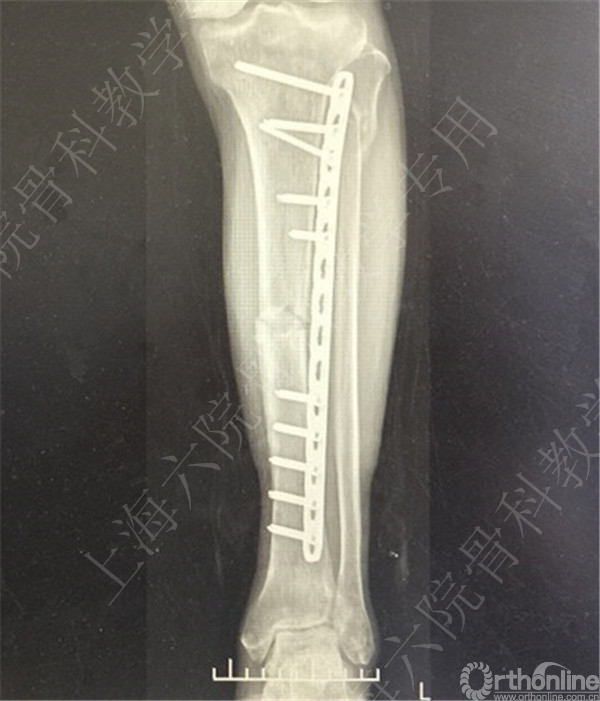

患者择期行左胫骨切开复位内固定术+髂骨异体骨植骨。

术后X线摄片示:骨折对位对线可,内固定牢靠,左胫骨对线可。

医方第一次跟换内固定术中,未纠正左胫骨立线,骨折对位对线差,未纠正成角,导致术后内固定失效,骨折成角变大。医方存在手术方式不当,手术操作不当,术后并发症观察、处理不当,对疾病评估不足,告知缺陷等过失。